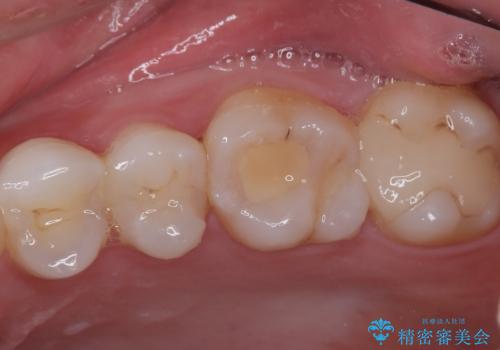

拡大鏡視野下で詰め物と虫歯の除去を行い、詰め物の範囲が大きかったためオールセラミッククラウンに適した形に整えました。

型どりはシリコーン印象材にて精密印象をしています。

歯がしみることがなくなったと大変喜んでいただけました。

適合もよく、機能的に問題もなく、見た目も満足されていました。